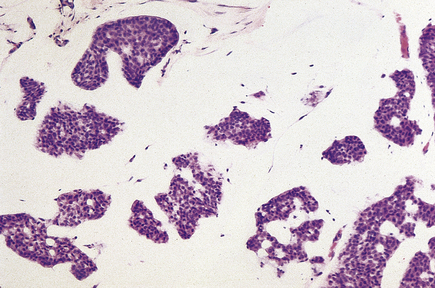

Papillary carcinomas

Papillary carcinomas are rare tumours that occur in post-menopausal women. They are usually circumscribed and can be focally necrotic, with little stromal reaction. The tumours are in the form of papillary structures, and areas of intraductal papillary growth are usually found.

The prognosis of patients with these carcinomas is probably better than that of the much more common invasive duct carcinoma.